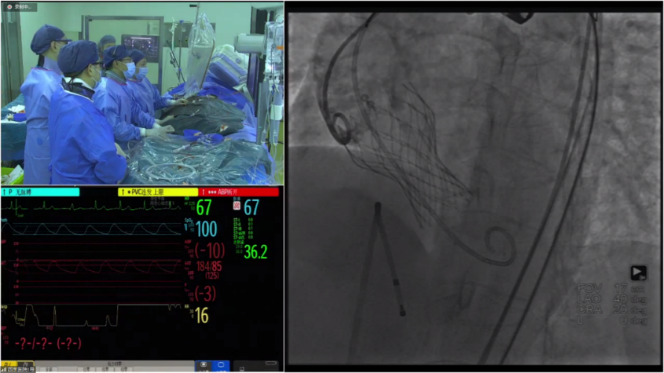

结合患者特殊的瓣环结构和整体入路情况,决定进行植入Evolut PRO 23mm瓣膜,配合自带内联鞘递送系统,考虑患者安全,术中备用snare辅助。但在实际过弓过程中,递送系统顺应患者超小的弓部顺利前进,在无阻力的情况下顺利跨过此例手术的第一个难点部位,至此手术仍具挑战,患者Type0型二叶瓣结构,瓣膜增厚且无钙化,导致瓣膜很难定位,在展开过程中,深度过高或过低都会导致瓣膜移位,经过两次稳定回收再释放,瓣膜达到预期位置稳固定位,无冠脉阻挡,无传导阻滞发生,术后压差<10mmHg,血流动力学稳定,手术圆满成功。

过弓

释放

释放后造影

后扩